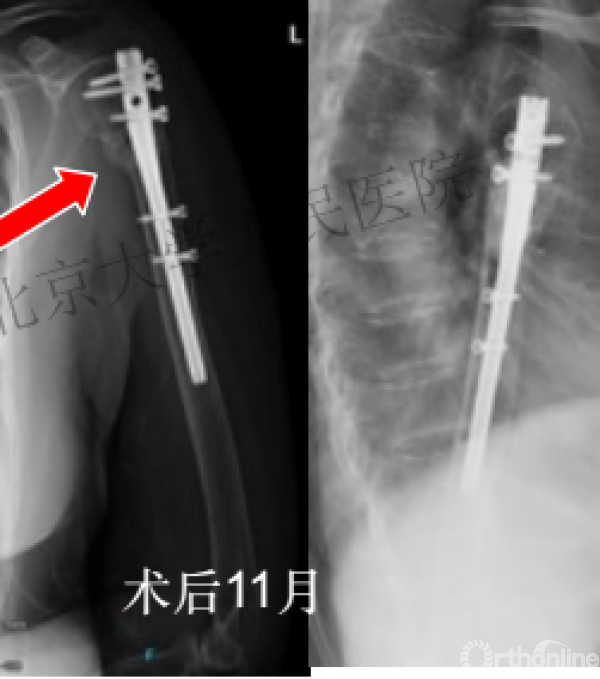

术后3月随访:继发性颈干角变小22°(5-82),肱骨头内翻,达46%

严重影响了患者的生活质量